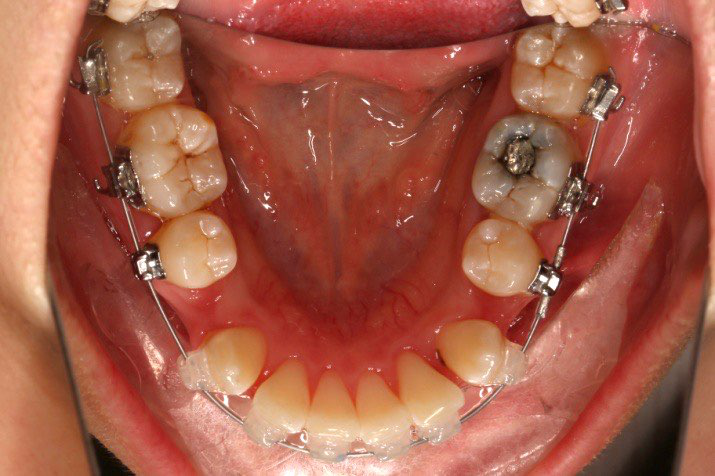

IntraoralExamination(2016-08.31,Wu)

1.第0个月:2016.10.31 ◆ 初戴,0.013cu-niti

2.第2.5个月:2017.1.13 ◆ 上颌加TPA,植入1312-08种植钉,上下0.16cu-niti

3.第3.5个月:2017.02.16 ◆ 上下0.014*25 cu-niti,50g 尖牙远中

2016.10.31  初戴,0.013cu-niti2017.1.13  上颌加TPA,U56间斜形植入韩国庆北1312-08种植钉,上下0.16cu-niti

2017.02.16  上下0.014*25 cu-niti,50g 拉尖牙远中